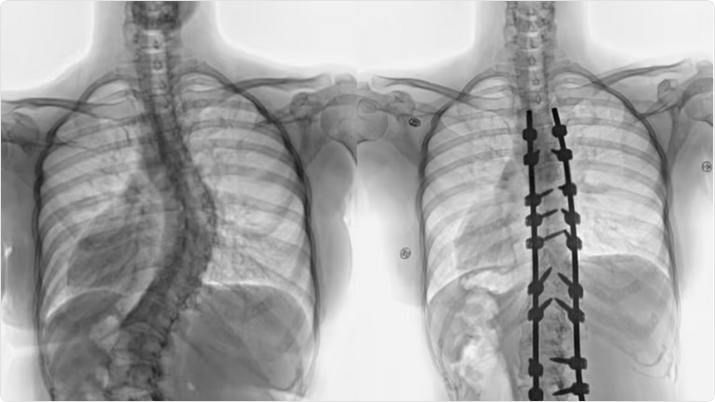

وقال د. خليفة أن المريضة راجعت المستشفى وهي تشتكي من انحناء جانبي للعمود الفقري منذ صغرها، بدأت مؤخراً تعاني من آلام بالظهر، إضافة إلى صعوبة في ممارسة الحياة الطبيعة، أدت هذه الأعراض إلى تغيير نمط حياتها والحد من حركتها، وفور وصولها إلى المستشفى أجريت لها التحاليل والفحوصات الطبية الدقيقة، التي بينت إصابتها بحالة انحراف “جنف” مضاعف بدرجة الـ”60″ للفقرات الصدرية، ودرجة 50 للفقرات القطنية ودرس الفريق الطبي الحالة على ضوء نتائج الفحوصات والتحاليل، وخلص إلى ضرورة التدخل الجراحي لعلاج العيوب، والحد من المضاعفات، وبعد اتخاذ كافة التدابير الطبية اللازمة لمثل هذه الحالات المعقدة، أخضعت الشابة لعملية جراحية، تم فيها تقويم العمود الفقري بعدد “20” من البراغي والقضبان المعدنية والطعوم العظمية الصناعية وتثبيت ودمج الفقرات، واستخدمت في العملية التي استمرت لـ”4″ ساعات، مع فريق تخدير متمرس ومراقبة أعصاب وفريق تمريض ماهر إضافة الى مجموعة من أحدث الأجهزة الطبية التي ساهمت مع الكوادر الطبية عالية الكفاءة والتأهيل بالمستشفى في إنجاحها.

ونقلت المريضة الى جناح التنويم بعد العملية، وبدأت حالتها في التحسن باضطراد بعد خروجها من غرفة العمليات، إذ استطاعت المشي بتوازن بعد أقل من “24” ساعة من العملية مع فريق العلاج الطبيعي المتمرس، واستعادت قدرتها على الاستلقاء والنوم على ظهرها، فضلاً عن القوام والمظهر الطبيعي، بعد تعديل وضعية الحوض والكتف، كما أن طولها مع النجاح الكبير للتعديل زاد بحدود “3” سم، وخرجت من المستشفى وهي بصحة جيدة، وتوقع أن تستعيد كامل عافيتها سريعاً مع الإنتهاء من برنامج العلاج الطبيعي.